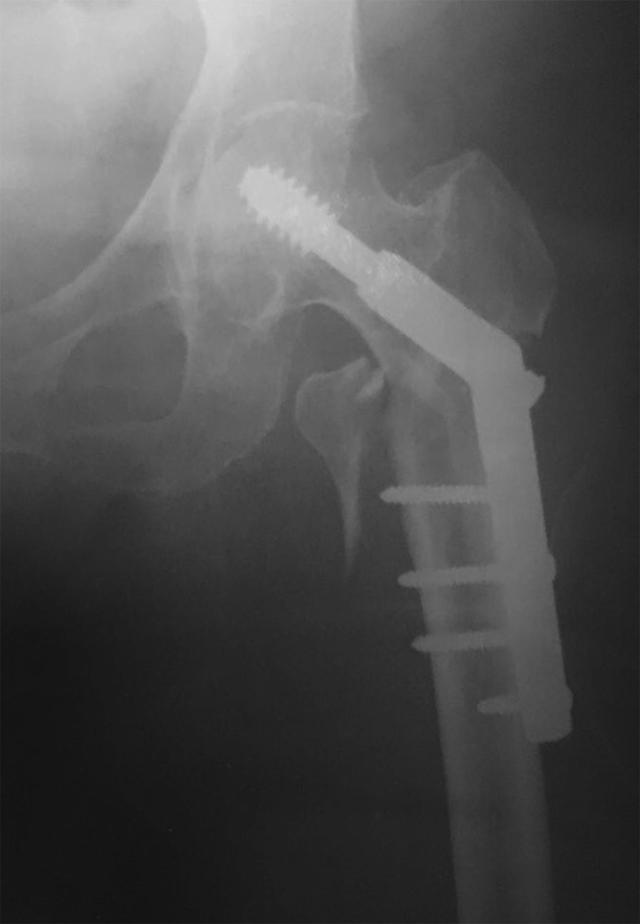

We report a case with implant failure after nailing of an unstable pertrochanteric fracture with dynamic hip screw. The patient presented with a medial sided thigh pain at 5 years after the surgery. Plain radiographs showed nonunion of the fracture with distant migration of assembled hip screw and side plate to the subcutaneous area of the inner thigh.

我们报告了一例采用动力髋螺钉治疗不稳定型转子间骨折后出现植入物失败的病例。该患者在术后5年出现大腿内侧疼痛。X线平片显示骨折不愈合,组装好的髋螺钉和侧板向大腿内侧皮下区域远距离移位。